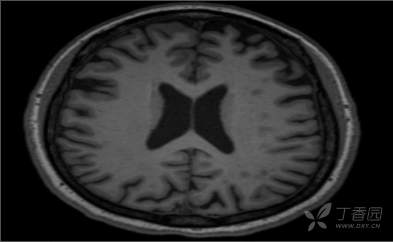

颈部、脑部动脉均未见明显异常,MRI+MRA+T2Flair+SWI+冠状位: 双侧额顶叶皮层下散在小缺血灶;双 侧海马萎缩2级,小脑蚓部、右侧额 叶微出血灶,如下图所示: